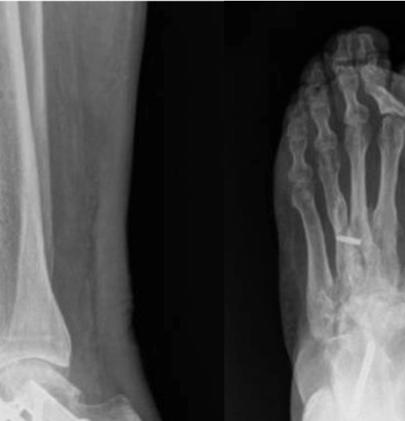

4fordatacollectiontools.)Thrombotic eventswerecollectedduringindexhospitalizationandat30 and90daysafterdischarge.Wedefinedthromboticeventsas deepveinthrombosis(DVT),pulmonaryembolism(PE), ischemicstroke,myocardialinfarction,orotherarterialor venousthromboembolicevents.Doortoneedletimewas definedastimefromhospitalpresentationtoreceiptof reversalagent.OnsettoCTtimewascalculatedusingthe differencebetweeninitialCTandtimeofbleedingonset, wheretheybothexisted;onsettoCTtimefortheremainder ofcaseswasdeterminedbycombiningcategoricalonsetto presentationtime(<6,6–12,12–24,24–48,and >48hours),

usingthemediantimeforeachcategory,withdoortoCT time.Wedefinedallstudydataandvariablespriorto initiatingthestudyandtrainedourdataabstractorsusinga libraryofdefinitions(see Supplement1).Weperiodically monitoreddatacollectionandprovidedfeedbacktothedata abstractorsduringandafterdatacollectionandentry regardingmissing,conflicting,orobviouslyerroneousdata. Thenumberofdataabstractorsateachinstitutionvaried from1–3.Thedataabstracterswerenotblindedtotherapy.

Outcomes

Wedevelopedallstudyoutcomesapriori.Theprimary outcomeswerepresenceofestimatedtimesfromlastdoseof FXa-Iandtimefrombleedingonsettoadministrationof 4F-PCCorandexanetalfa.Secondaryoutcomeswere hemostaticefficacyasdefinedbytheANEXXA-4criteria,23 survivaltohospitaldischarge,thromboticeventsduringthe indexhospitalizationandat30and90days,andrebleeding eventssuchasICH,rectalbleeding,melena,orhematemesis.

DataAnalysis

Weuseddescriptivestatisticstosummarizethedata. Categoricaldataarepresentedasnumbersorpercentages andcomparedbetweengroupsusingchi-squareorFisher exacttestsasappropriate.Continuousvariablesare presentedwithmeansandstandarddeviationsormedians andinterquartileranges(IQR)basedontheirdistribution andcomparedwith t -testsortheMann-WhitneyUtests,as appropriate.Becausethiswasapilotstudy,noformalsample sizecalculationwasperformed.Wechosetoinclude25 patientsineachofthefourstudysubgroups:ICHtreated withandexanetalfa;ICHtreatedwith4F-PCC;GIBtreated withandexanetalfa,andGIBtreatedwith4F-PCC.An exploratoryPSMmodelwasconstructedtoestimatetheodds ofexcellent/goodhemostaticefficacyinpatientstreatedwith andexanetalfaor4F-PCCadjustingforage,gender, comorbidities,timefromlastdoseofFXa-I,time frombleedonsettotreatment,andindication foranticoagulation.